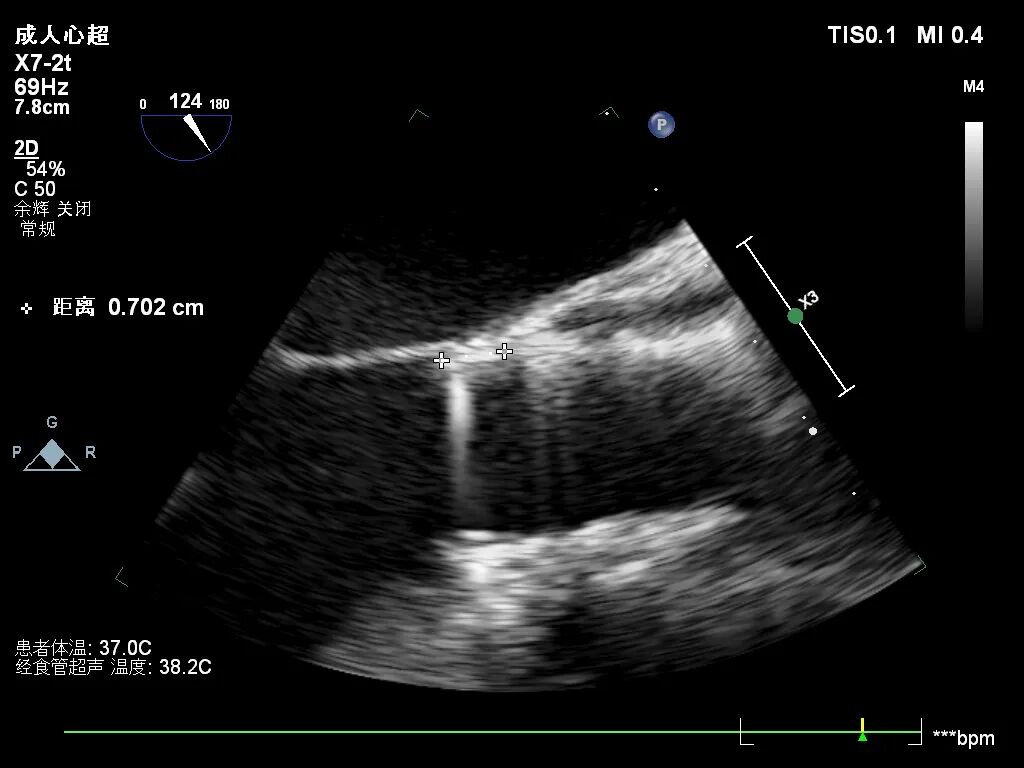

手术过程概览

主动脉根部造影,反流明显

瓣上3mm定位

释放到工作位下滑至零位

瓣架打平,同轴性好

超声看左冠窦侧6mm左右

完全释放,无反流

超声看完全释放下滑至7mm

几乎无反流

几乎无瓣周漏

观察后无下滑